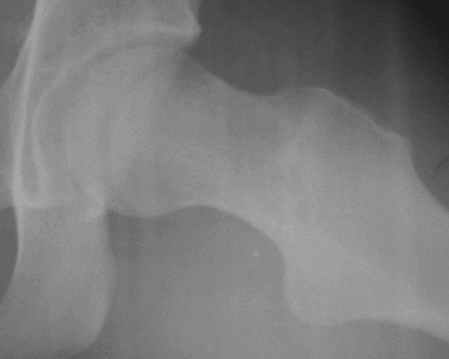

Уважаемые коллеги! Заканчивая обследование больного с переломо-вывихом бедра сделал ему обычные R-томограммы. Кажется удалось "поймать" и отломок и донорское место. Мои выводы - в скиаграмме. Считаю, что это передне-нижний фрагмент головки, образовавшийся вследствии отрывного перелома. На томограммах отломок обозначаю длинной стрелкой, а место откуда он оторвался - более короткой. Учитывая тот факт, что его размеры по КТ 25 х 15 мм считаю, что его фиксация на место необходима для профилактики артроза, что при 16-ти летнем возрасте пациента важно в плане максимального отодвигания эндопротезирования. Планирую оперировать его 24.05.05 г. Результаты представлю.

Прямой при поступлении

Прямой 19.05

Несколько соображений к "картинкам". На прямом снимке и КТ-томограммах все типичные линии вертлужной впадины: крыша, передняя стенка, задняя стенка - сохранены. На КТ-сканах 6 и 7 появляется фрагментация головки. С учетом R-томограмм отломок расположен спереди-снизу, а не сзади-сверху от сустава, как написано в описании КТ.